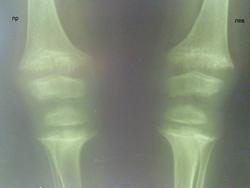

Девочка, 3 года 8 мес. направлена детским хирургом, по анамнезу - около 2 месяцев нарушение походки, прихрамывает на лев. ногу, периодически болят коленки. По описанию движения в суставах не ограничены. Направлена на Р-грамму коленных суставов с диагнозом: Болезнь Блаунта? и на Р-грамму тазобедренных суставов с диагнозом: Болезнь Пертеса слева? Врожденный вывих бедра?

Ваше мнение, коллеги по данной паталогии, проявления рахита или еще что-то?

Думаю - тяжелый рахит... Справа вальгусная деформация бедра - увеличен шеечно-диафизарный угол.

На снимках коленных суставов типичные признаки рахита: отсутствие замыкательных пластинок, бокаловидная деформация, расширение зон роста, костные балки "торчат". Но загвоздка в том, что признаки рахита должны проходить к двум годам, а ребенку больше трех лет, значит надо дообследовать почки и кишечник - искать откуда вымывается кальций - поздний рахит на ровном месте не бывает.

Исключаем рахитоподобные заболевания. Насколько я в курсе, именно для них характерны более поздние, чем при классическом рахите, костные деформации. Ребенка надо направлять к педиатру и (особенно) к нефрологу для более подробного дообследования.

Дифференциальный диагноз классического Витамин D-дефицитного рахита проводят, прежде всего, с различными вариантами так называемых рахитоподобных заболеваний:

Витамин D-зависимый рахит I и II типа

Витамин D-резистентный рахит:

- Фосфат-диабет

- Синдром Дебре – де Тони – Фанкони

- Почечный тубулярный ацидоз

- Гипофосфатазия